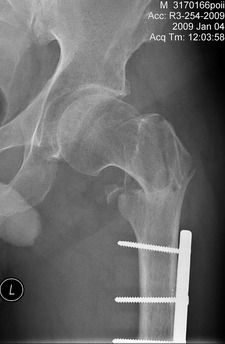

Больной 42 лет получил перелом проксимального отдела бедра. Ранее (1 год назад) оперирован на том же бедре по поводу оскольчатого диафизарного перелома. Четкой консолидации диафизарного перелома на рентгенограммах нет. Сопутствующие заболевания - tbs и гепатит С. При обсуждении хотелось бы услышать варианты лечения 1) "в идеале" и 2) с учетом социального статуса. Спасибо, А.Ситник

Р-гр шейки

Теперь ситуация более ясная. Оптимальным тут, очевидно, было бы малоинвазивное удаление пластины и закрытый интрамедуллярный остеосинтез длинной гаммой или другим проксимальным гвоздем. Это не только обеспечило бы надежную фиксацию всех проблемных отделов бедра, но и позволило бы немедленную полную нагрузку.

Другие варианты менее привлекательны, хотя в итоге могли бы привести к успеху. Но ценой большей травматичности, длительности лечения, неудобств, трудоемкости и с бОльшими рисками неприятностей. Вариантов очень много - скелетное вытяжение, тазобедренная повязка, остеосинтез DHS или другой пластиной с угловой стабильностью, остеосинтез таким или другим аппаратом...